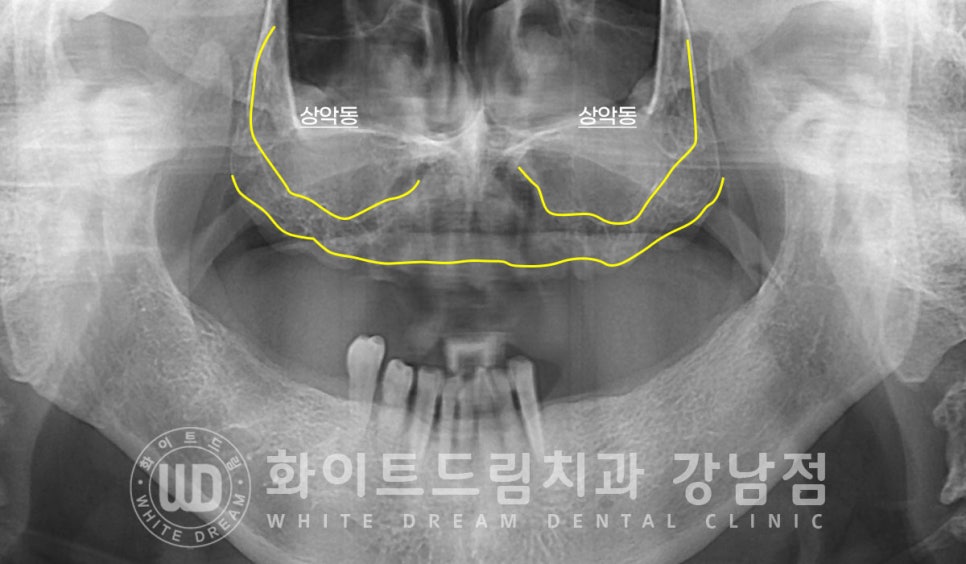

우리 얼굴뼈 속에는 상악동(Maxillary sinus)이라는 빈 공간이 있는데요.

머리뼈의 무게를 줄여주고 숨을 쉴 때 폐로 들어가는 공기들의 온도 & 습도를 조절하는

역할을 하는 공간이랍니다.

이 공간이 치아를 발치하게 되면 치아 뿌리가 있던 부위의 잇몸뼈가 흡수되기 시작하면서

잇몸뼈가 점점 얇아지게 되고 상악동이 팽창하게 됩니다.

이러한 과정을 상악동 함기화라고 한답니다.